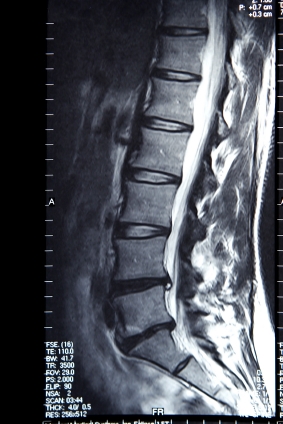

МРТ поясничного без красителей

Описание услуги - МРТ поясничного без красителей

МРТ является магнитно-резонансная томография, специальный тест визуализации, которая не использует рентгеновских лучей. МРТ в нижней части спины можно определить связок, мышц, нервов, диски, кости и спинной мозг. Это самый лучший тест для обнаружения артрит, грыжа межпозвоночного диска, спинного инфекции, повреждение спинного мозга, повреждения нерва, и рак спины и спинного мозга.